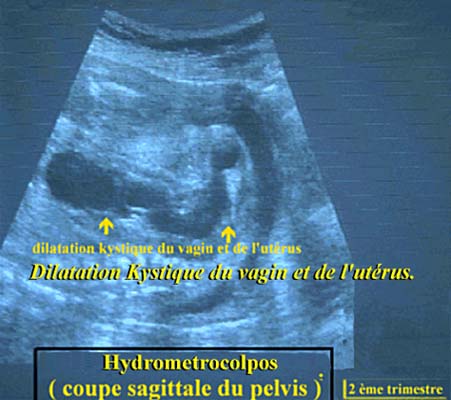

L’hydrométrocolpos est une dilatation kystique du vagin et de l’utérus secondaire à une obstruction basse. Le mucus des glandes cervicales stimulées par les œstrogènes maternels s’accumule en amont de l’obstacle, dilatant le vagin, l’utérus voire les trompes de Fallope avec passage péritonéale.

L’obstacle à l’écoulement du mucus peut-être dû à une imperforation hyménéale, à une membrane vaginale à une atrésie vaginale ou peut-être dû à une embryopathie plus complexe telle qu’une anomalie du sinus urogénital.

C’est une malformation rare puisque sa prévalence est de 1/30000 naissances.

En échographie anténatale l’hydrométrocolpos apparaît comme une masse pelvienne hyperéchogène ovulaire située derrière la vessie et en avant du sacrum.

Son contenu peut-être échogène en raison de particules mucoïdes, des

cloisons peut-être observées ainsi qu’un niveau de sédimentation.